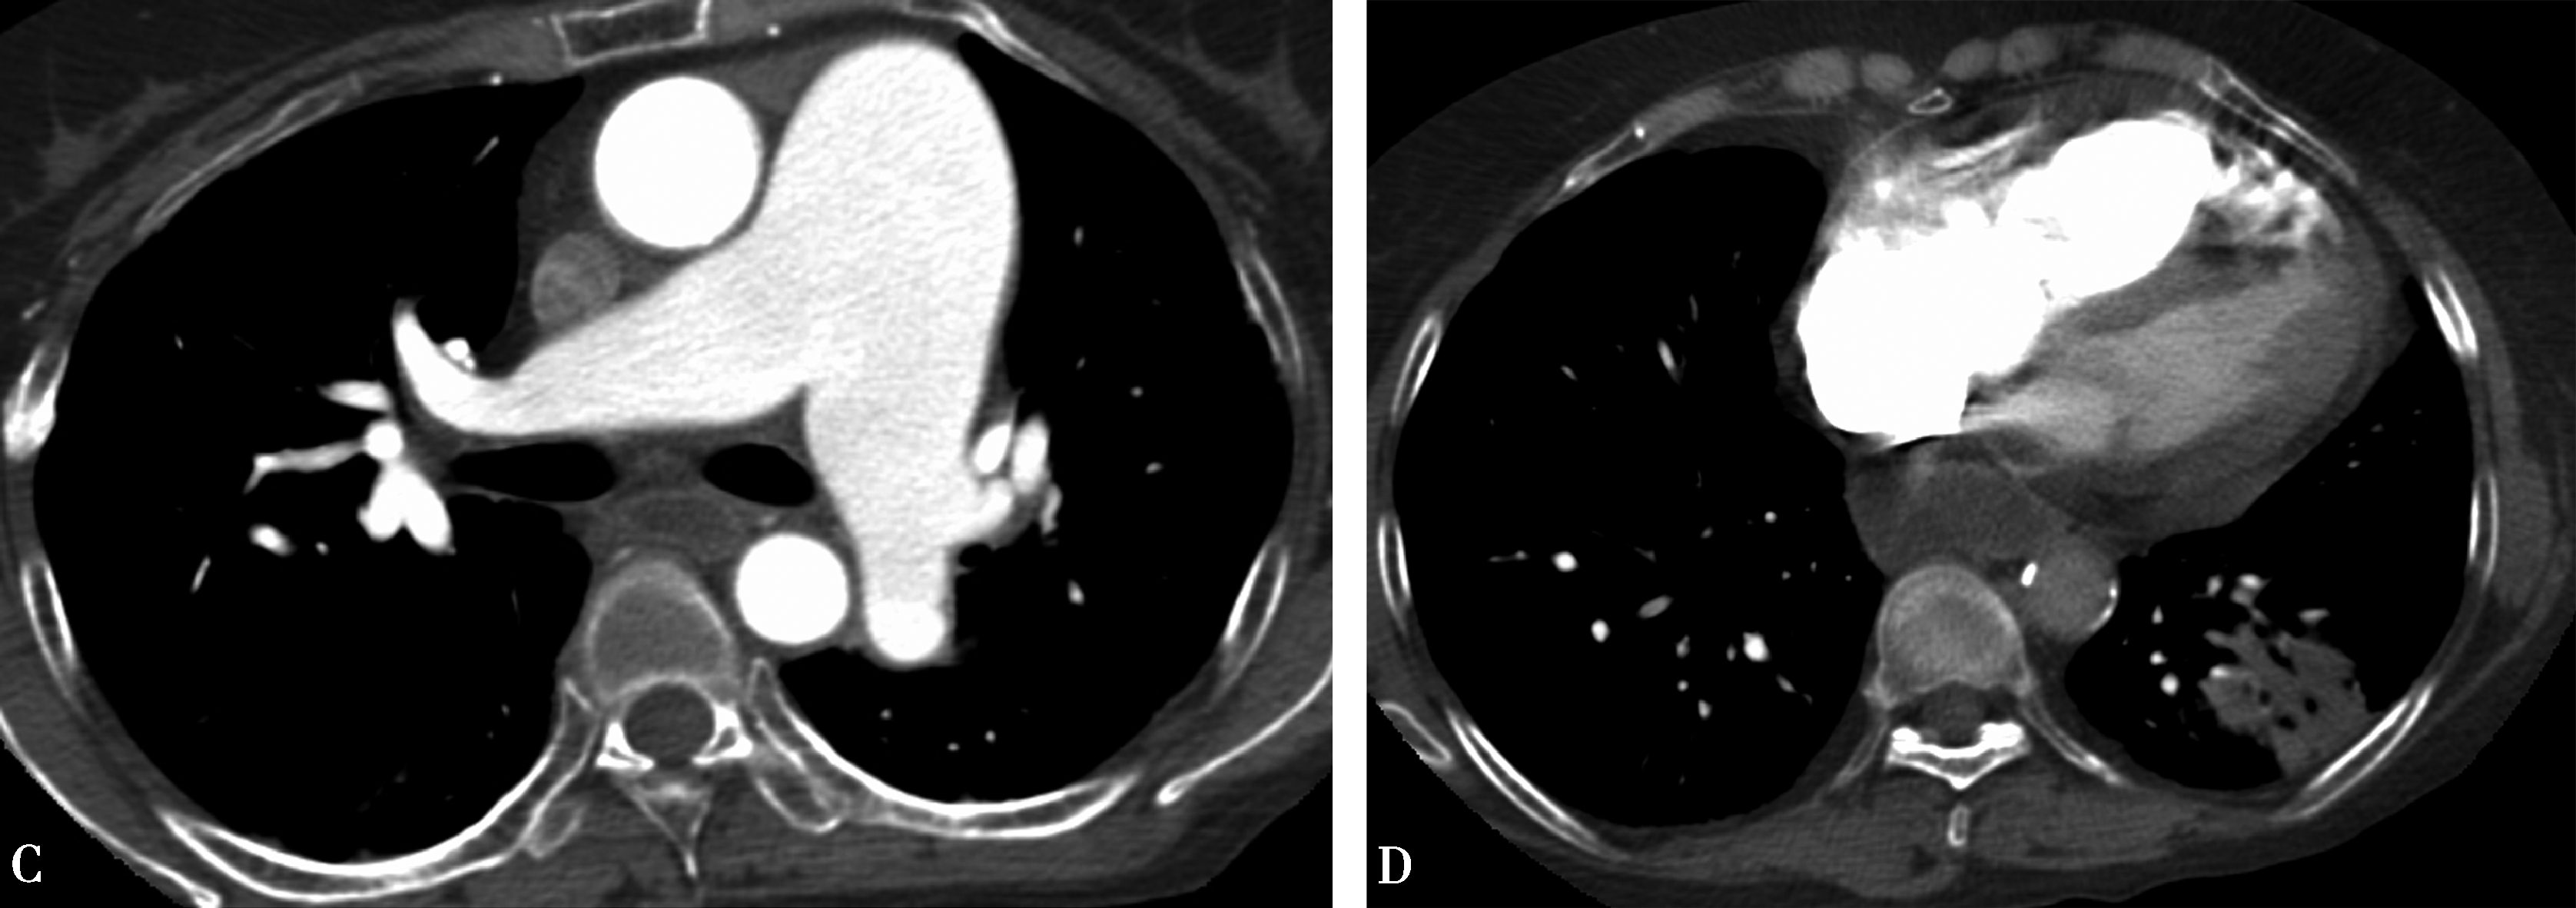

3.右心功能不全CT征象

右心功能不全表现为:①右心房、室增大;②上腔静脉增宽、奇静脉增宽、下腔静脉增宽有反流现象;③心包积液;④胸腔积液(图8-3-12)。

图8-3-12 肺动脉高压右心功能不全

A.肺动脉高压,右心衰竭;右心增大,上、下腔静脉增宽(↑);B.多层重组示奇静脉(△)、下腔静脉增宽有反流现象(↑);C.横断图像示上腔静脉增宽(↑)